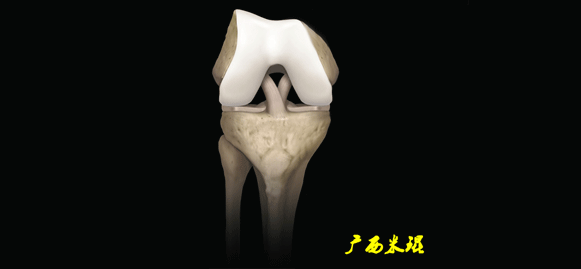

膝关节结构较复杂

(二)ACL的正常MRI表现

各序列均为低信号。

韧带平直,边界清楚,有较好的张力。

韧带内可有脂肪及滑膜条纹影。